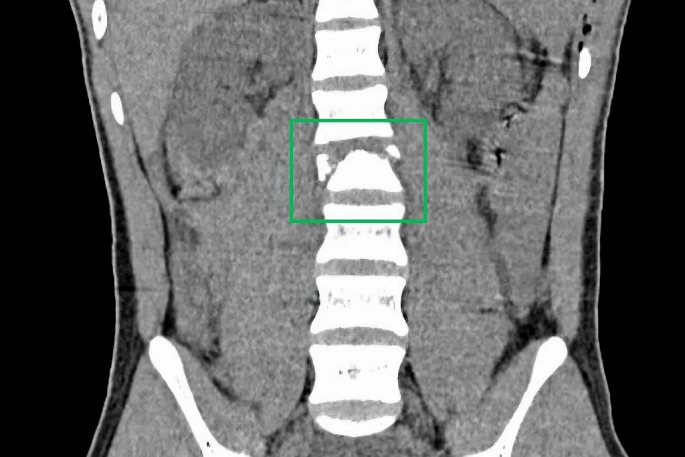

Hình ảnh chụp cắt lớp cho thấy bệnh nhi T.N.Đ bị gãy xẹp đốt sống L2. Ảnh: BVCC

Theo người nhà, trẻ bị trượt ngã khi đang đi xe máy. Sau khi ngã, trẻ bị đau hai chân và được đưa vào bệnh viện địa phương. Tại bệnh viện, các kết quả chẩn đoán hình ảnh cho thấy trẻ bị gãy xương sống, đứt tủy, xương sống gãy vỡ phức tạp nên được chuyển khẩn cấp vào Bệnh viện Nhi Đồng 2.